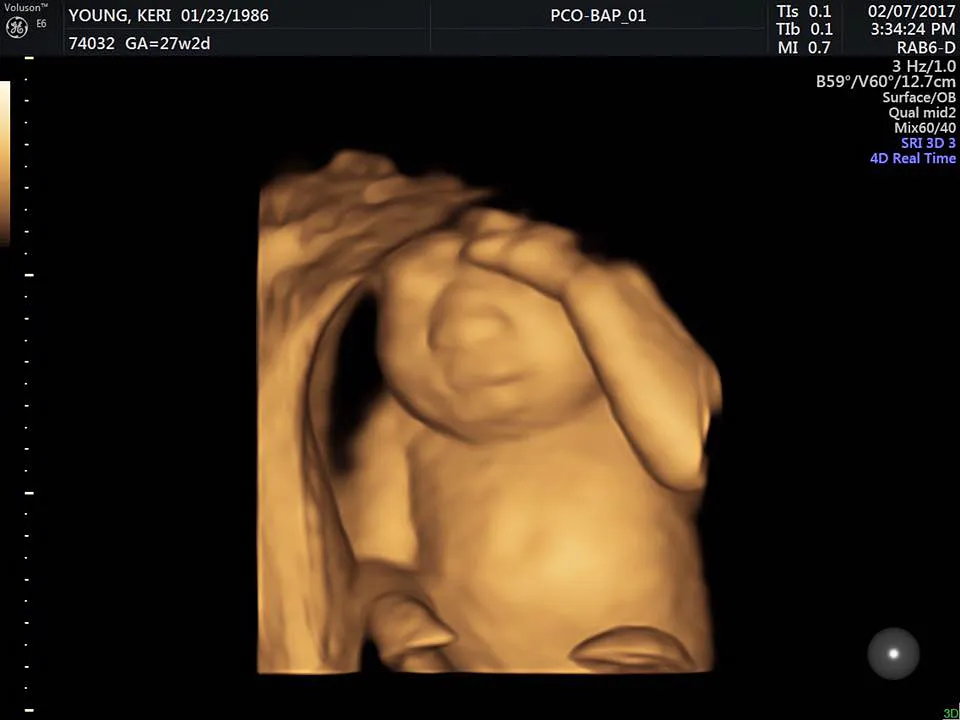

Pregnant Keri Young has been documenting her unborn daughter’s progress on Facebook, recently posting a 4-D ultrasound of the baby, who she and her husband, Royce Young, have named Eva.

“It was so, so amazing. She has chubby cheeks and long fingers and toes,” she wrote of the baby, due May 7. “Everything is still measuring as it should and seeing her today made us more excited than ever to hold her.”

“This is our daughter’s perfect heart. She has perfect feet and perfect hands. She has perfect kidneys, perfect lungs and a perfect liver. Sadly, she doesn’t have a perfect brain. We found out recently she has anencephaly and is terminal. Faced with terrible options we have decided to continue the pregnancy to full term so Eva, which literally means life, can grow strong and give life to multiple people through organ donation.”